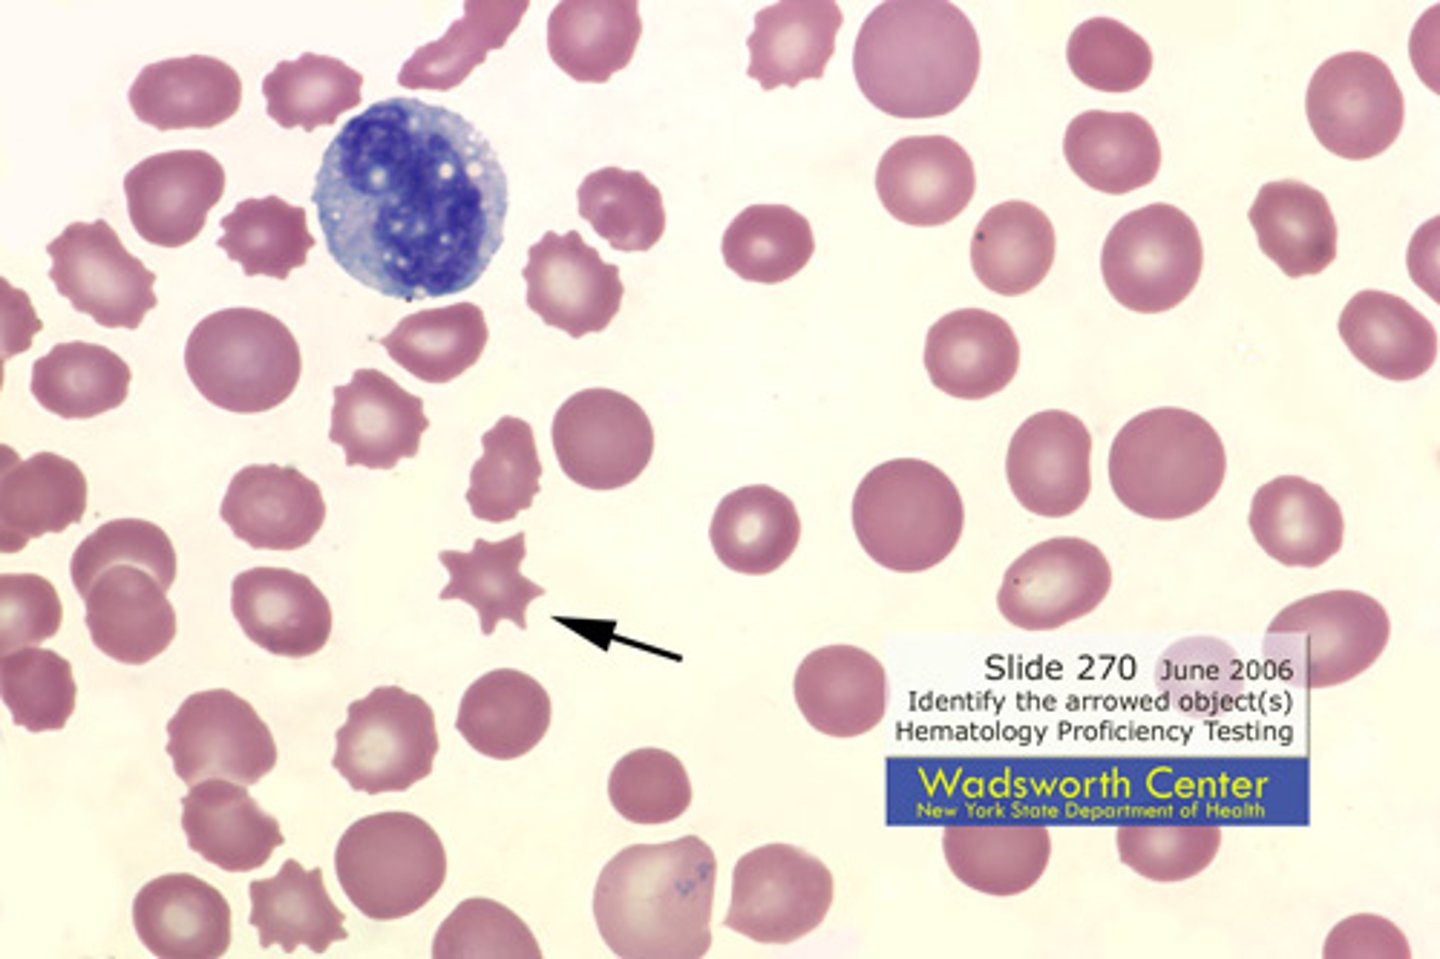

acanthocyte

MAMMAL

multiple (2-10), IRREGULARLY shaped and spaced fingerlike projections

- nickelodeon sign

crenation

UNIFORM, evenly spaced, short projections around the RBC's

mainly caused by artifact "old" blood

- too much anticoagulant to blood ratio